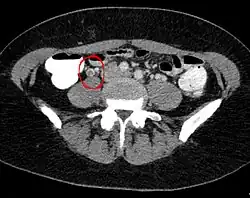

Die Erkrankung tritt meist zwei bis sechs Tage postpartal auf. Entscheidend für die Diagnose sind bildgebende Verfahren (CT) sowie Laboruntersuchungen (Leukozyten und CRP).